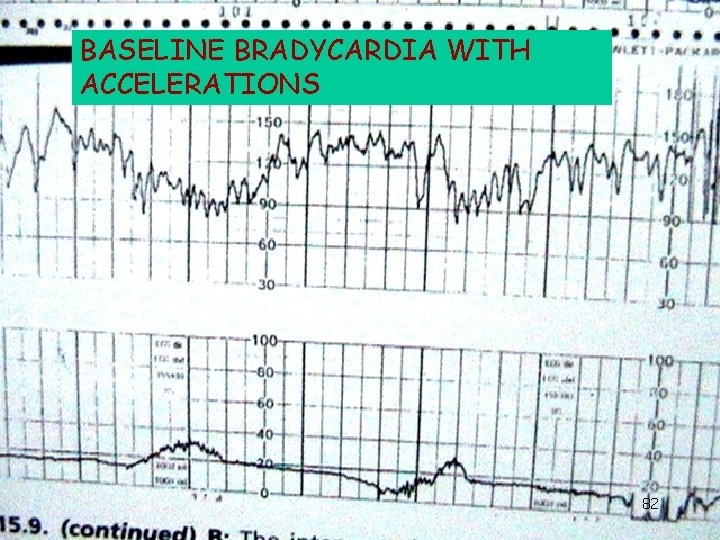

BASELINE BRADYCARDIA WITH ACCELERATIONS 82